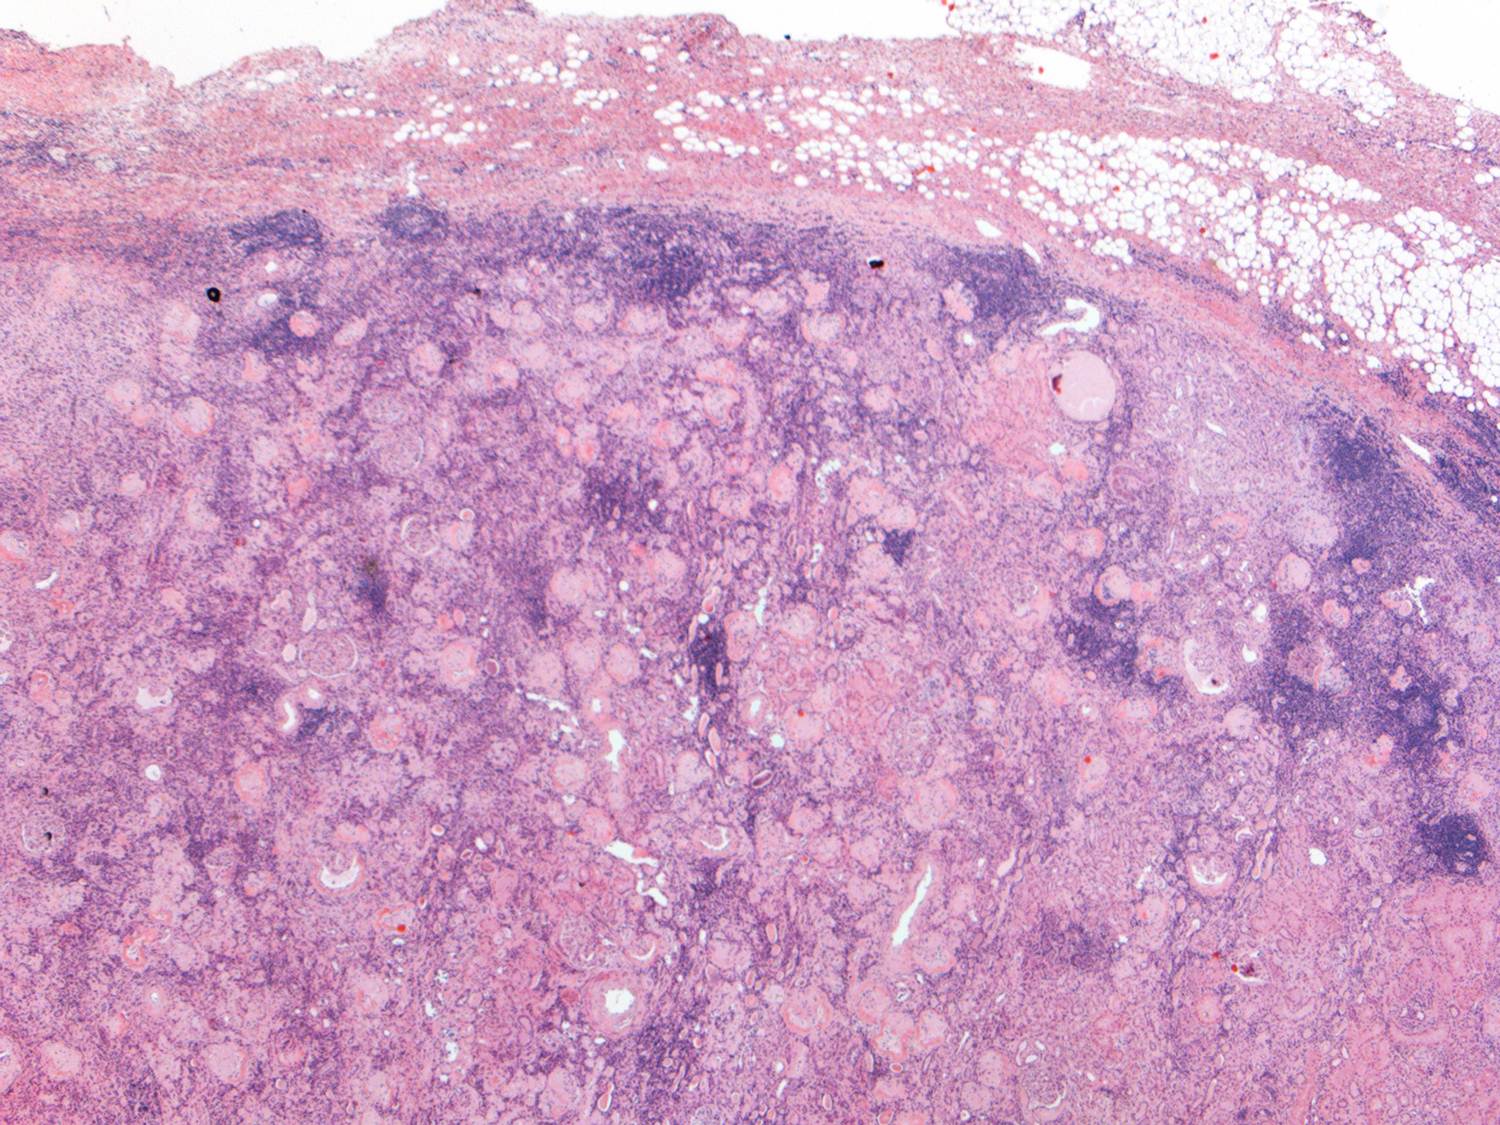

Study from France analyzed 302 patients with biopsy-proven rejection and identified 4 subtypes of acute rejection with different outcomes (Figure): T-cell-mediated vascular rejection (9%), antibody-mediated vascular rejection (21%), T-cell-mediated rejection without vasculitis (46%), and antibody-mediated rejection without vasculitis (24%). Antibody-mediated vascular rejection manifested a median of 1.1 months (0.4–4.4) post-transplant and had the worst prognosis of the four subtypes. Moreover, 71% of cases of vascular rejection, which were mostly graded as v1 and v2 arteritis by the Banff schema, were associated with donor-specific antibodies (DSA).